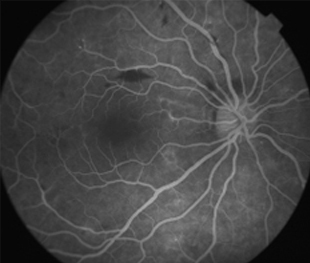

2 meses: disminución de manchas algodonosas y hemorragias con mejoría de circulación

Funcional

OD - 0,50 esf 0,9 +2

OI -0,25 esf 1,00